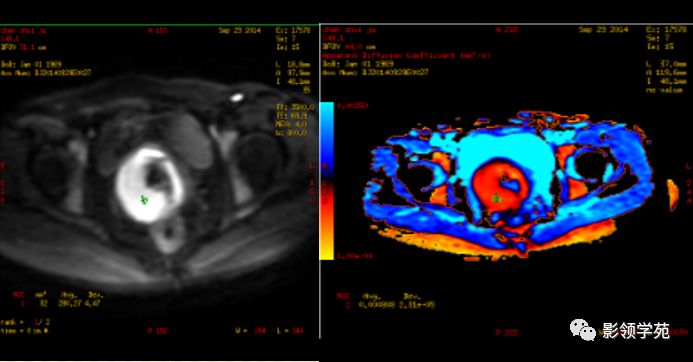

DWI:局限性高信号,癌组织ADC值<癌旁组织<小于正常宫颈组织

Ⅰ期